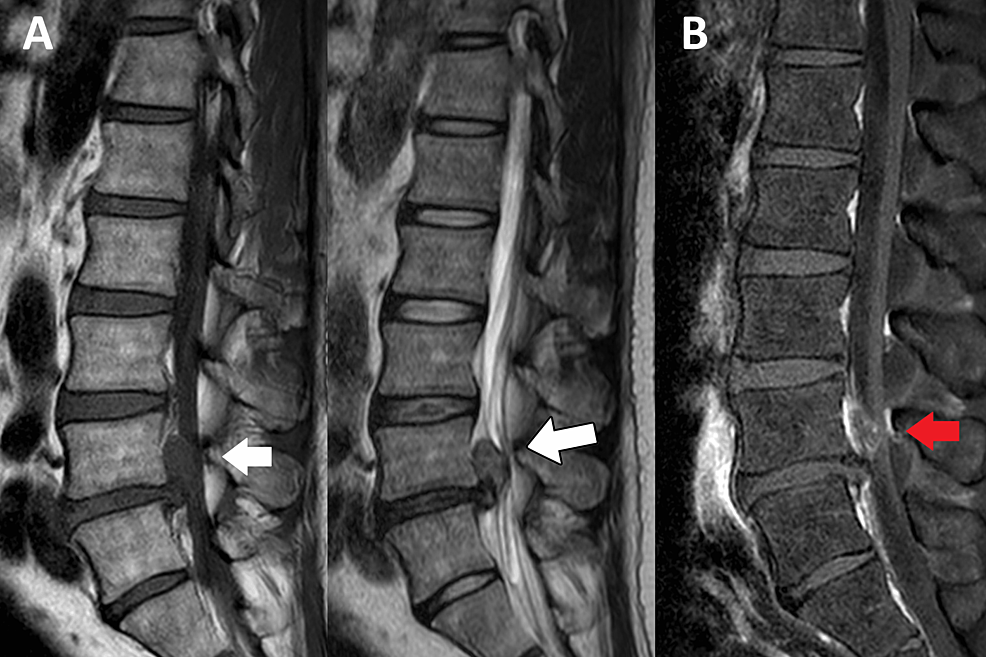

Your spine contains soft, gel-like discs between each vertebra. These intervertebral discs act as shock absorbers and help with movement and flexibility. When injured, the disc material can move beyond its normal boundaries, causing pain and inflammation.

- Disc Bulge – A general broadening of the disc without rupture of the outer layer

- Disc Protrusion – Focal displacement of disc material, where the outer layers are still intact

- Disc Herniation – The inner nucleus pushes through a tear in the outer layer (annulus)

- Disc Extrusion – The disc material breaks through the annulus and may press on nearby nerves

- These conditions are often lumped together as a “slipped disc”, but each has different implications for pain and recovery.